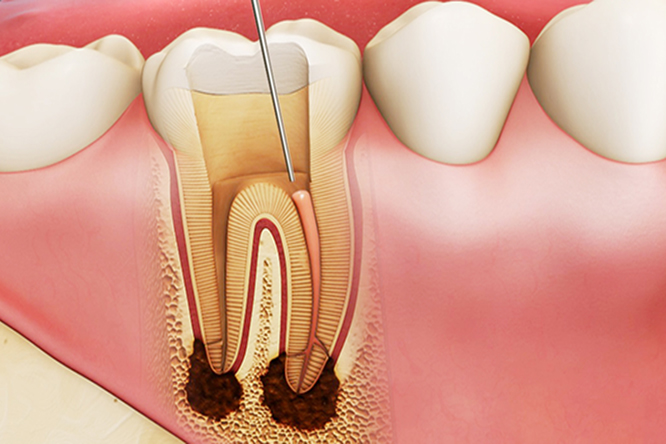

Điều trị tủy răng là phương pháp điều trị nội nha lấy bỏ tủy răng - một mô nhỏ dạng sợi ở chính giữa răng, sau khi lấy hết mô tủy bị hủy hoại, bị viêm hay bị chết tủy, khoảng trống trong ống tủy sẽ được làm sạch tạo thành ống tủy và sẽ được hàn kín lại bằng chất hàn nha khoa.

Cắt chóp răng là một thuật ngữ được sử dụng trong nha khoa được áp dụng trong trường hợp răng có biểu hiện viêm nhiễm có thể hư hỏng sâu bên trong răng làm chết tủy, nhiễm trùng chân răng… Cắt chóp răng với mong muốn loại bỏ vị trí viêm nhiễm mà không phải nhổ bỏ răng, cắt chóp răng sẽ có thể loại bỏ được hết phần chóp răng bị viêm nhiễm, ống tủy còn sót lại trong quá trình điều trị tủy.